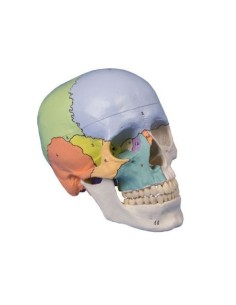

Dal cranio in 22 parti con incastri magnetici ai modelli di colonna vertebrale, da quelli di articolazioni a quelli di cuore, ogni pezzo della nostra collezione è progettato per un’immersione totale nello studio dell’anatomia umana. I nostri modelli, realizzati tramite scansioni di ossa vere, garantiscono un’esperienza tattile autentica e una fedeltà di peso quasi identica agli originali.